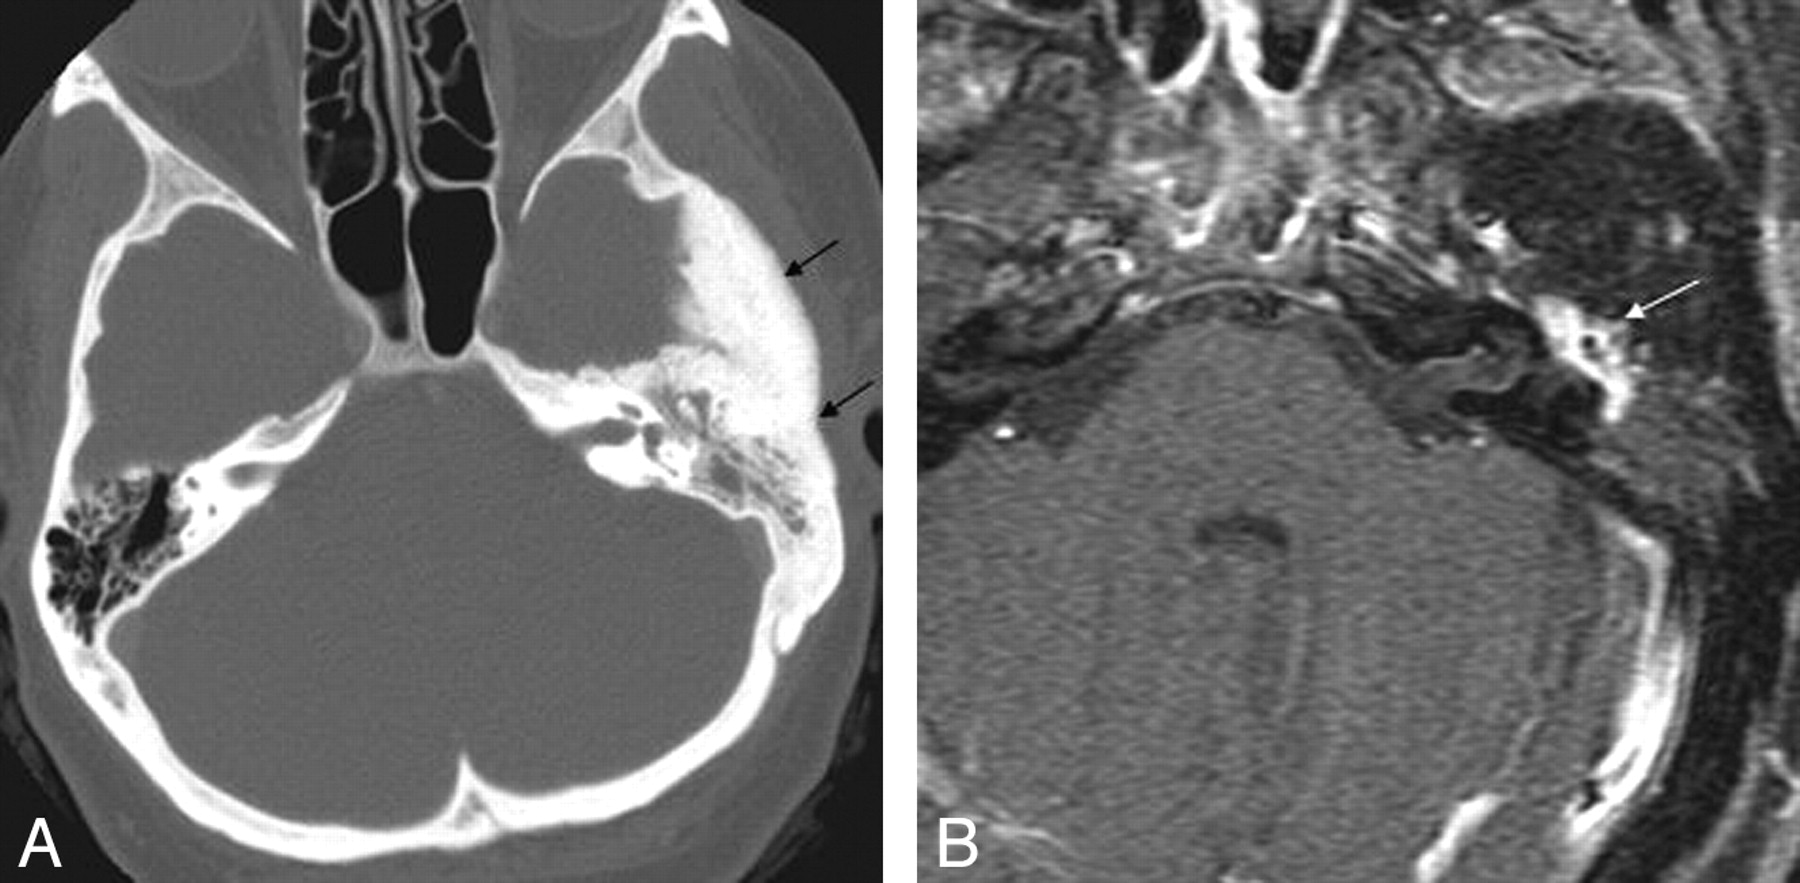

On axial CT images, an aberrant ICA is seen as a tubular structure running horizontally through the middle ear from posterior to anterior (Fig 2A). The inferior tympanic canaliculus is enlarged, and the vertical segment of the petrous ICA is absent. The aberrant ICA is often smaller than the contralateral normal ICA19 and may be difficult to detect on conventional MR imaging. On MR angiography, the aberrant ICA extends more laterally than its normal course. This has been termed the 7 or reversed-7 sign (Fig 2B).20

Aberrant course of the ICA in a 25-year-old man presenting with pulsatile tinnitus. A, Enhanced axial CT image demonstrates an abnormal lateral course of the right ICA through the middle ear (white arrow). Also note dehiscence of the overlying bony plate. B, Anteroposterior projection image from the MR angiogram of the same patient demonstrates decreased caliber and lateral deviation of the aberrant ICA on the “right reversed-7 sign” (black arrow).

Intraosseous meningiomas of the temporal bone or skull base can occasionally present with tinnitus28 and mimic sclerotic fibrous dysplasia on imaging. CT characteristically demonstrates thickening of the tegmen tympani, but the internal trabecular architecture of the involved bone is preserved (Fig 6A). This feature has been termed “trabecular” hyperostosis to distinguish it from the bone thickening observed in cortical hyperostosis or fibro-osseous lesions. Characteristic MR imaging findings include en plaque linear dural enhancement along the floor of the middle cranial fossa and homogeneous soft-tissue enhancement (Fig 6B).29

Intraosseous temporal bone meningioma in a 45-year-old woman who presented with left-sided hearing loss and tinnitus. A, Axial CT image demonstrates diffuse sclerosis of the temporal bone and soft-tissue attenuation (black arrows) in the left mastoid and middle ear cavity. B, Axial enhanced MR image in the same patient demonstrates enhancement within the left middle ear (white arrow).